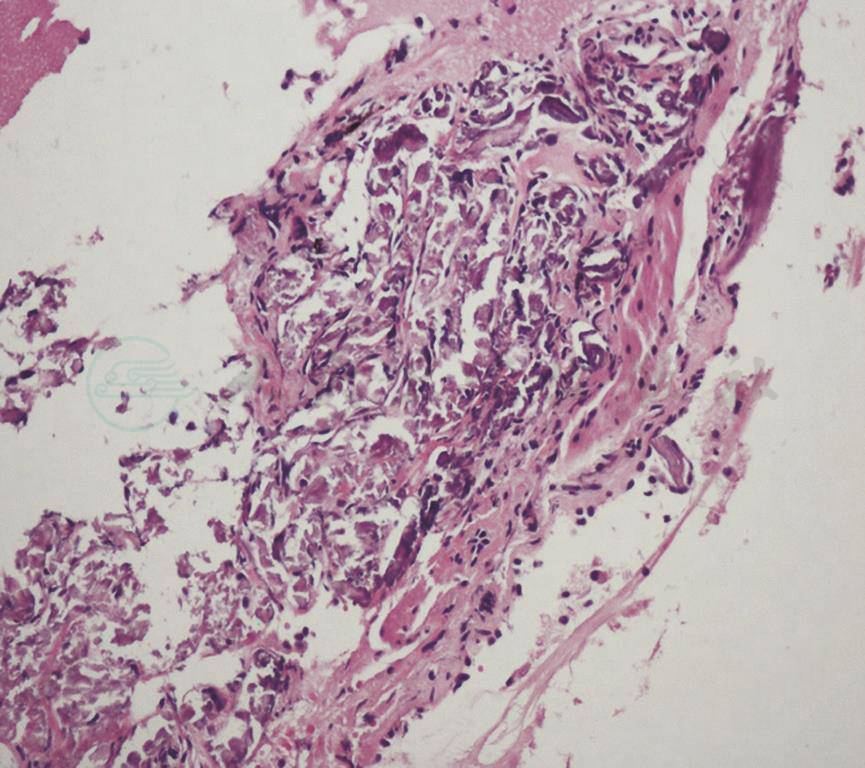

镜下见双肺各叶段支气管通畅,未见气管、支气管内明显异常。支气管肺泡灌洗液抗酸杆菌涂片阴性。经支气管肺活检(TBLB)见右肺下叶肺泡腔及肺泡隔多量钙化物沉积(图4)。

图4 经支气管肺活检病理结果(HE染色,200×)

引自:主编:.呼吸系统疑难病例诊疗辨析.第1版.ISBN:978-7-117-26415-0

MPC通常无症状,少数患者可出现呼吸困难,甚至呼吸衰竭。由于血钙升高可致钙盐沉积在正常肺泡、肺泡间隔、支气管壁、肺血管壁等,病理表现为肺泡及肺泡间隔钙质沉着,肺组织变硬,肺泡间隔增宽,进而发生纤维化。呼吸困难症状与钙盐肺内沉积过多导致限制性功能障碍及弥散功能障碍有关。本例患者以活动后气喘为主要表现,可能与大量钙盐沉积于肺部,导致肺通气及弥散功能障碍有关。及早诊断并治疗原发病对于改善MPC患者的症状及疾病预后有非常重要的作用。

根据辅助检查结果,考虑本病例病因为原发性甲状旁腺功能亢进,手术切除甲状旁腺,病理检查显示为甲状旁腺腺瘤。甲状旁腺激素分泌过多可致高钙、低磷。本例患者钙磷乘积在正常范围内,经支气管肺活检见肺泡腔及肺泡隔有多量钙化物沉积,胸部CT见两肺散在斑片状影,99mTc-MDP骨闪烁显像见双侧肺野骨外显影,排除了肺结核、矽肺等常见疾病。因此,本病例诊断为甲状旁腺腺瘤伴发转移性肺钙化。